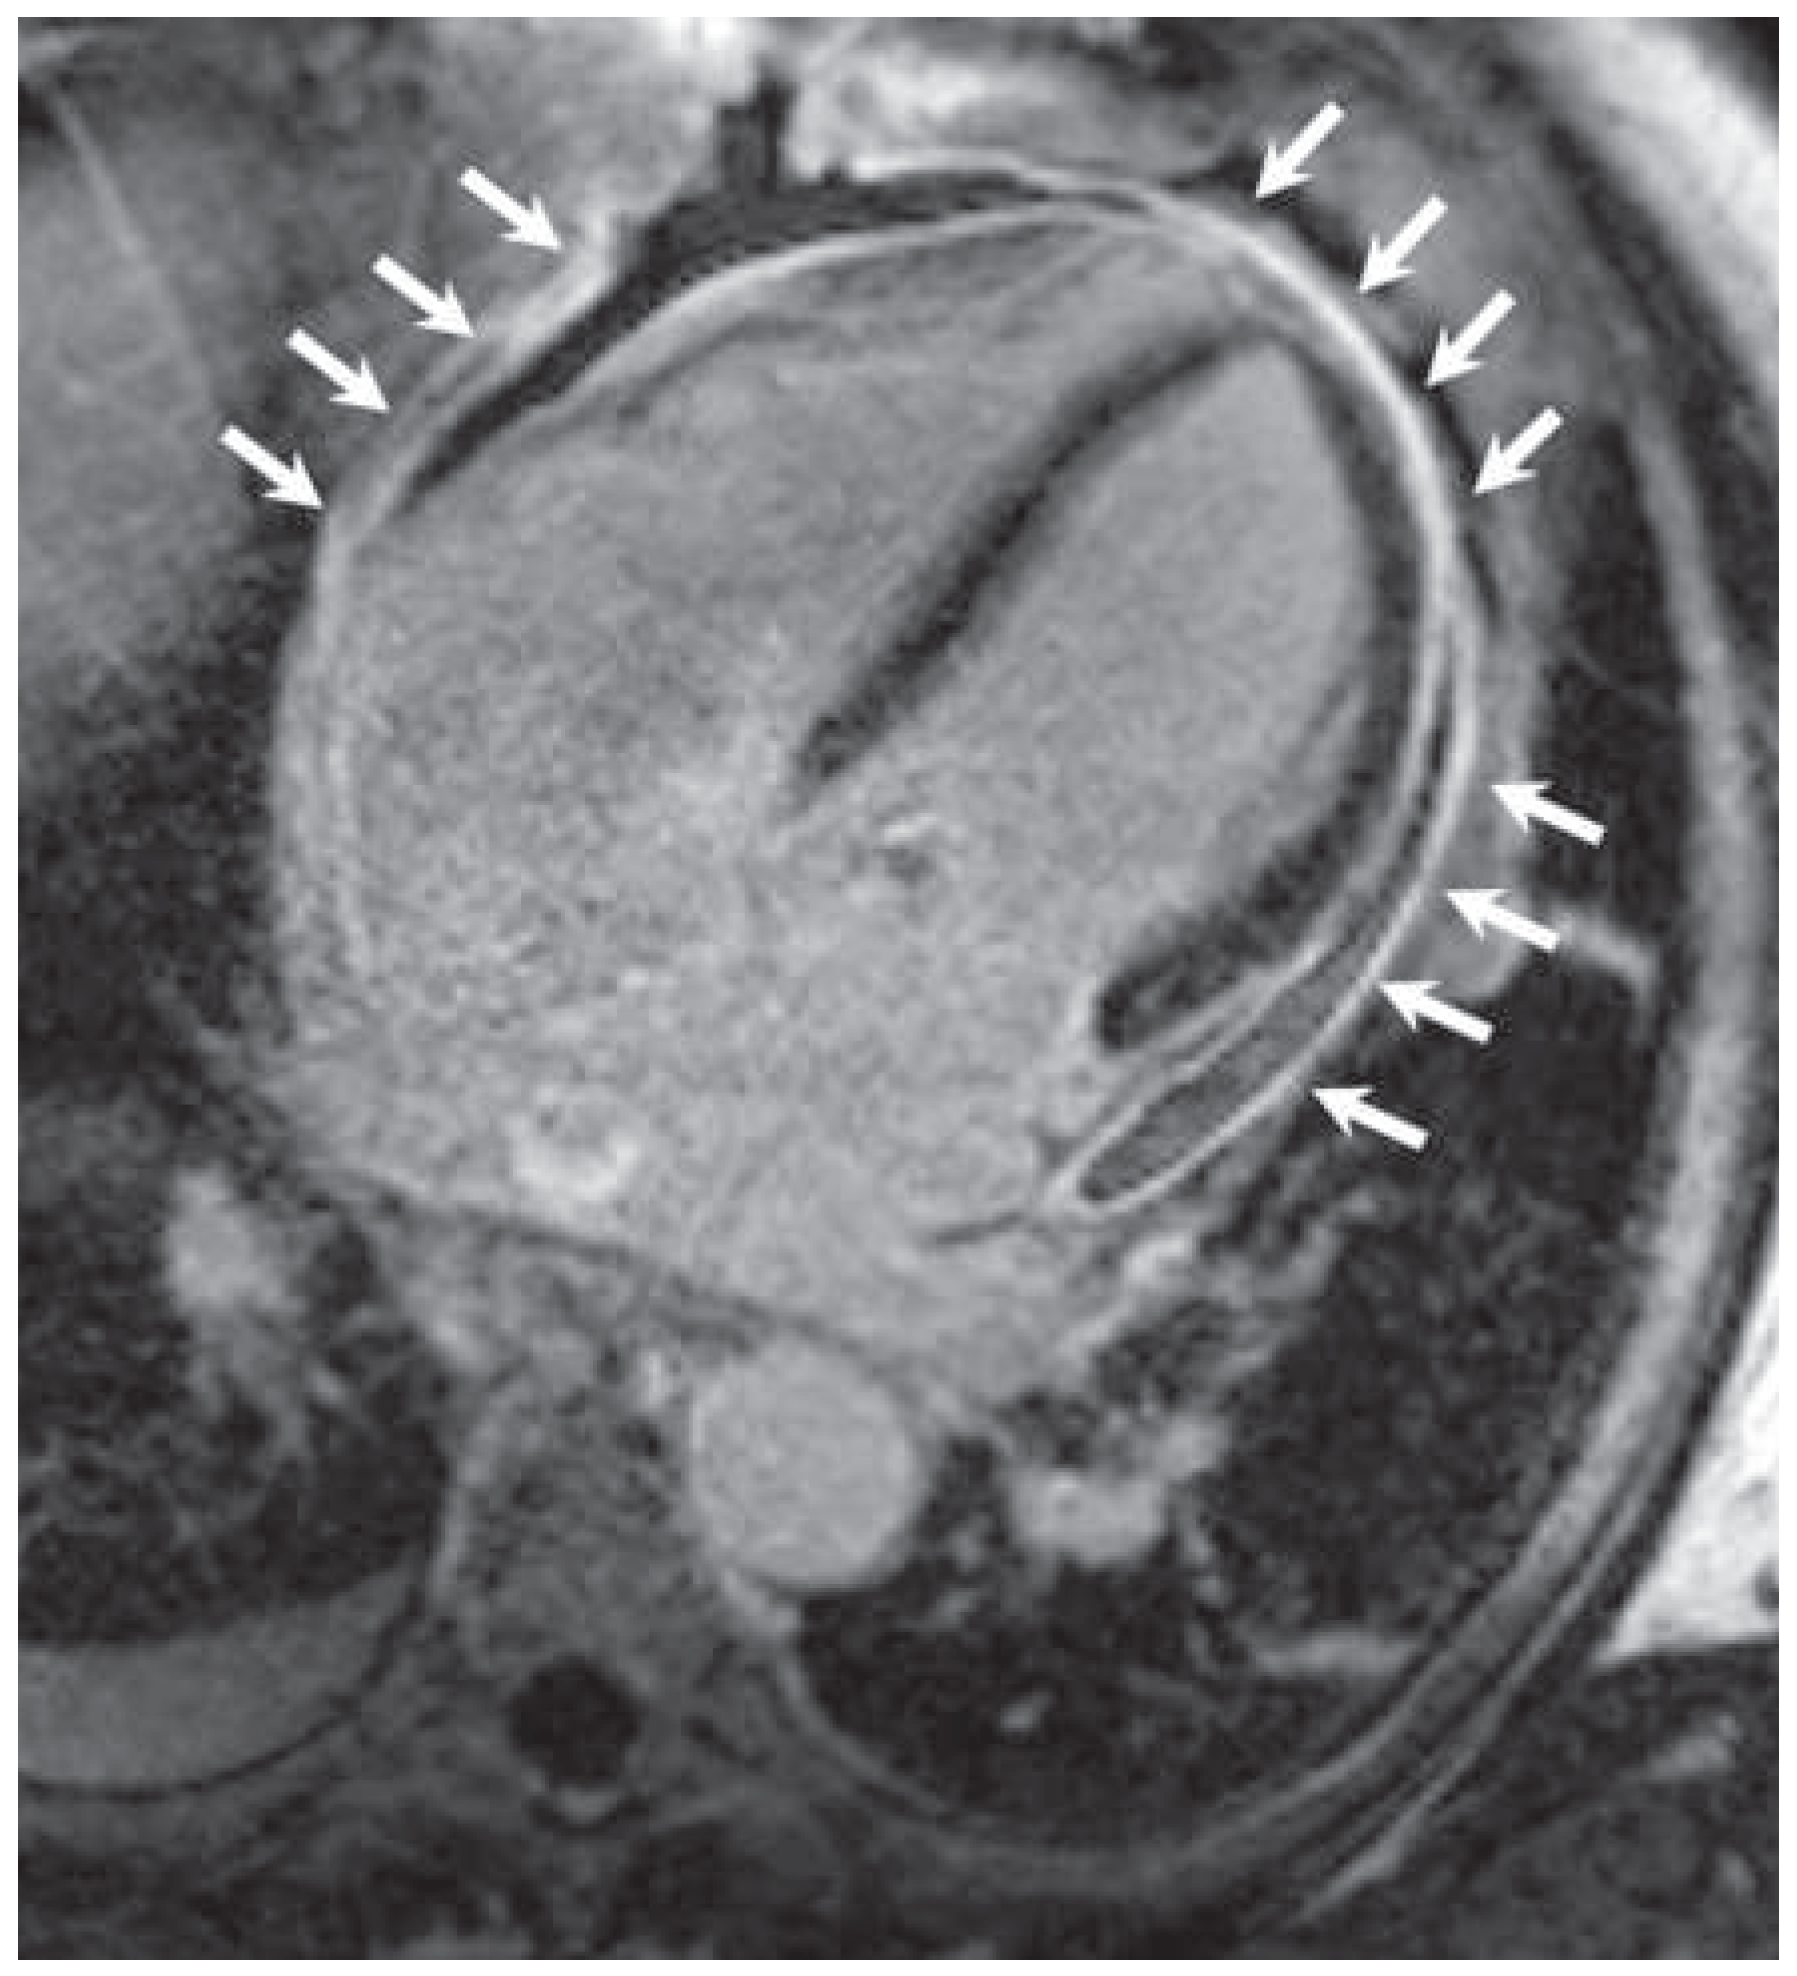

Kussmaul's Sign in Effusive Constrictive Pericarditis